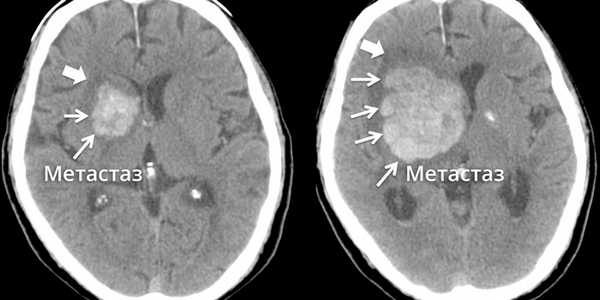

Для обнаружения опухоли используются методы нейровизуализации. Золотым стандартом её является выполнение МРТ с и без контрастирования. Если МРТ недоступна или у пациента есть противопоказания к её выполнению (клаустрофобия, наличие в теле предметов из ферромагнетиков), проводят КТ с контрастным усилением или без него. Дополнительную информацию можно получить с помощью ПЭТ, КТ-ангиографии или дополнительных режимов МРТ. Необходимо иметь ввиду, что внутривенное контрастирование существенно увеличивает эффективность КТ, а при выполнении МРТ - позволяет значительно более качественно обнаруживать злокачественные опухоли, в том числе метастазы небольших размеров без перифокального (то есть образующегося вокруг них) отёка.

Метастазы в головном мозге.

Метастаз в головном мозге в динамике

«Золотой стандарт» в диагностике метастатического рака головного мозга — магнитно-резонансная томография (МРТ). Во время этого исследования получают изображения внутренних структур тела, используя сильное магнитное поле. По снимкам врач может судить о количестве, размерах, расположении метастатических очагов.